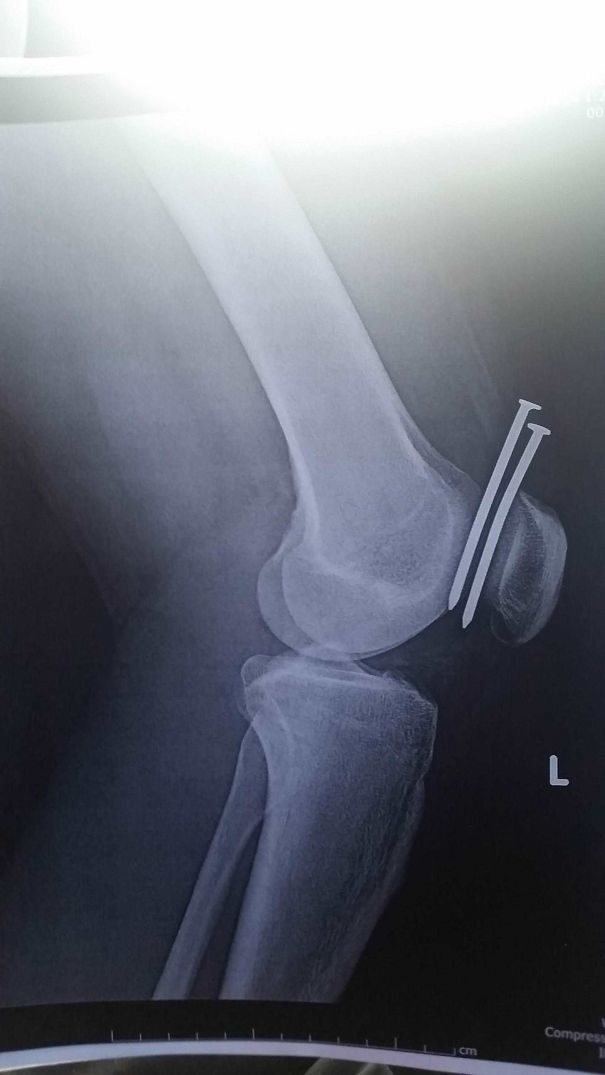

11. God must be looking down on this guy. He avoided contact with both his femur and kneecap.